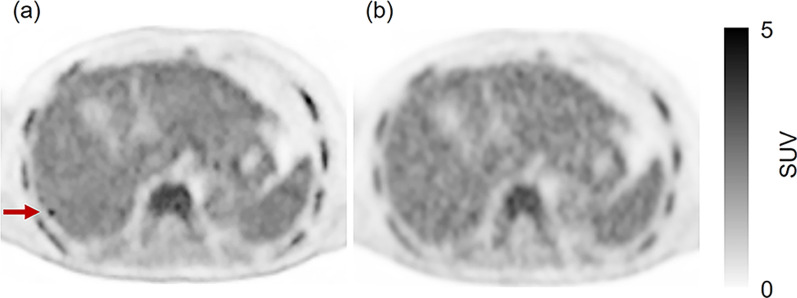

Background: A deep learning-based image reconstruction (DLR) algorithm that can reduce the statistical noise has been developed for PET/CT imaging. It may reduce the administered dose of 18F-FDG and minimize radiation exposure while maintaining diagnostic quality. This retrospective study evaluated whether the injected 18F-FDG dose could be reduced by applying DLR to PET images. To this aim, we compared the quantitative image quality metrics and the false-positive rate between DLR with a reduced 18F-FDG dose and Ordered Subsets Expectation Maximization (OSEM) with a standard dose.

Results: This study included 90 oncology patients who underwent 18F-FDG PET/CT. They were divided into 3 groups (30 patients each): group A (18F-FDG dose per body weight [BW]: 2.00-2.99 MBq/kg; PET image reconstruction: DLR), group B (3.00-3.99 MBq/kg; DLR), and group C (standard dose group; 4.00-4.99 MBq/kg; OSEM). The evaluation was performed using the signal-to-noise ratio (SNR), target-to-background ratio (TBR), and false-positive rate. DLR yielded significantly higher SNRs in groups A and B than group C (p < 0.001). There was no significant difference in the TBR between groups A and C, and between groups B and C (p = 0.983 and 0.605, respectively). In group B, more than 80% of patients weighing less than 75 kg had at most one false positive result. In contrast, in group B patients weighing 75 kg or more, as well as in group A, less than 80% of patients had at most one false-positives.

Conclusions: Our findings suggest that the injected 18F-FDG dose can be reduced to 3.0 MBq/kg in patients weighing less than 75 kg by applying DLR. Compared to the recommended dose in the European Association of Nuclear Medicine (EANM) guidelines for 90 s per bed position (4.7 MBq/kg), this represents a dose reduction of 36%. Further optimization of DLR algorithms is required to maintain comparable diagnostic accuracy in patients weighing 75 kg or more.